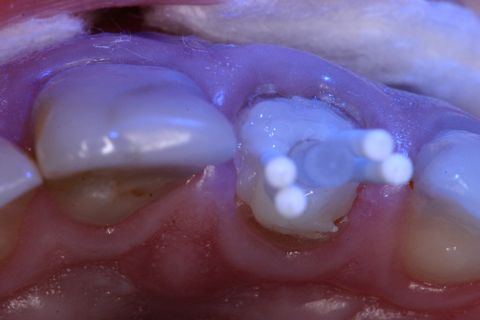

Aspecto clínico inicial (vista oclusal)

Pino de fibra de vidro #3 (Exacto) pinos acessórios (Reforpin) Angelus, Brasil

Resina Fill Magic NT Premium, Coltene - Vigodent, Brasil

Inserção da resina no remanescente dentário

Inserção do pino Exacto na resina

Inserção dos pinos acessórios na resina

Inicialmente, foi removido o tecido cariado do remanescente dental e realizado a seleção do pino de fibra de vidro (Exacto # 3, Angelus, Brasil) e também foram selecionados pinos acessórios (Reforpin, Angelus, Brasil) (Figuras 4).

Isolou-se o conduto radicular com óleo mineral e inseriu-se a resina composta (Fill Magic NT Premium, Coltene-Vigodent, Brasil) sobre o remanescente dentário com auxílio de uma espátula suprafill #1/2 (Figuras 5 e 6). Após o preenchimento do conduto com resina, foi inserido o pino Exacto cônico e os pinos acessórios previamente silanizados (Silano, Angelus, Brasil) e com a aplicação do adesivo (Fusion Duralink, Angelus, Brasil) (Figuras 7, 8 e 9). Em seguida, promoveu-se a fotoativação inicial do conjunto pino-resina por 20 segundos.